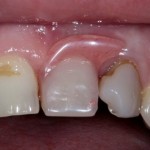

В таких случаях пациенту нередко предлагается какая-то съемная протетическая конструкция (в народе называемая «бабочкой» или «жучком»), задача которой — замаскировать отсутствие зуба до его восстановления с помощью импланта:

И, я должен заметить, что с маскировкой такой простейший протез отлично справляется: